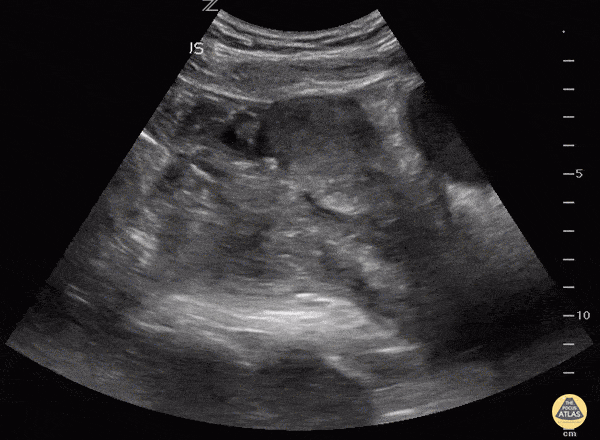

Always make sure the "IUP" is actually in the uterus by observing the uterus superior to the bladder in the sagittal view. This young lady could have been diagnosed easily with IUP and her abdomen pain dismissed as pain with pregnancy instead of a 10 week ectopic. Matt Rutz, MD @IUEM_Ultrasound Indiana University School of Medicine Department of Emergency Medicine Division of Ultrasound